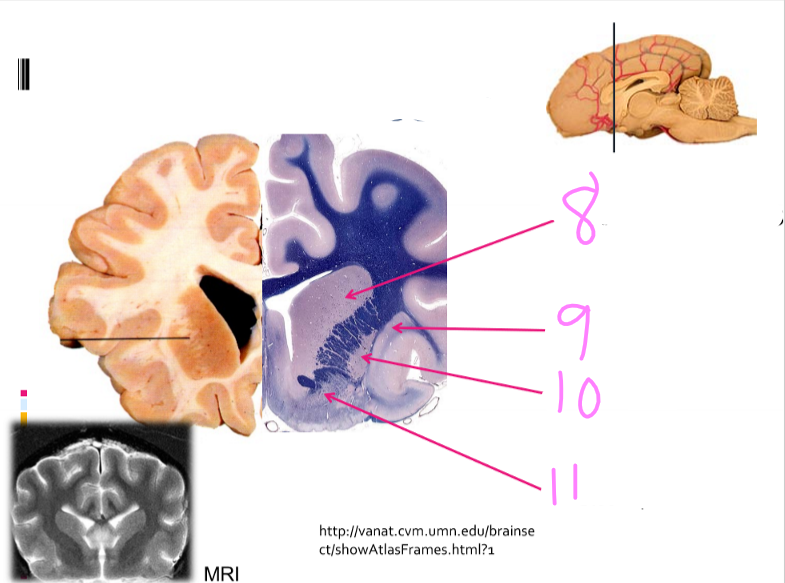

8

New cards

Caudate nucleus

9

Claustrum

10

Putamen

11

Globus pallidus